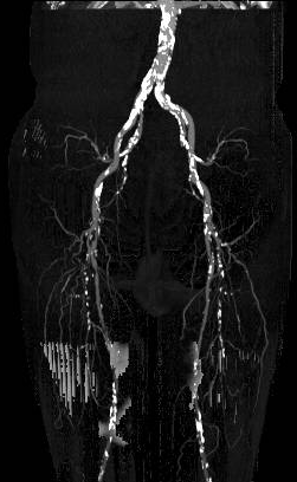

现病史:患者双下肢间歇性跛行5年余,跛距300米。后跛行症状加重伴双足发凉发麻跛距缩短至50米,右侧重、无静息痛、溃疡。下肢CTA提示:双侧股浅动脉重度狭窄近闭塞、右侧腘动脉重度狭窄

穿刺左股总动脉,置入6F股动脉鞘,双侧髂外、髂总动脉多发斑块,管腔轻度狭窄

以超滑导丝配合多用途导管、可调弯导管“翻山”至右侧股深动脉;交换Ampalz导丝,置入8F-45cm长鞘

步进造影:股浅动脉起始重度狭窄、中段重度狭窄,腘动脉远端重度狭窄、胫前动脉、胫后动脉闭塞

步进造影配合血管腔内超声诊断导管提示:股浅动脉全程、腘动脉、胫腓干动脉血流通畅,未见明显夹层、造影剂外溢,远端未见栓塞,膝下动脉如前。